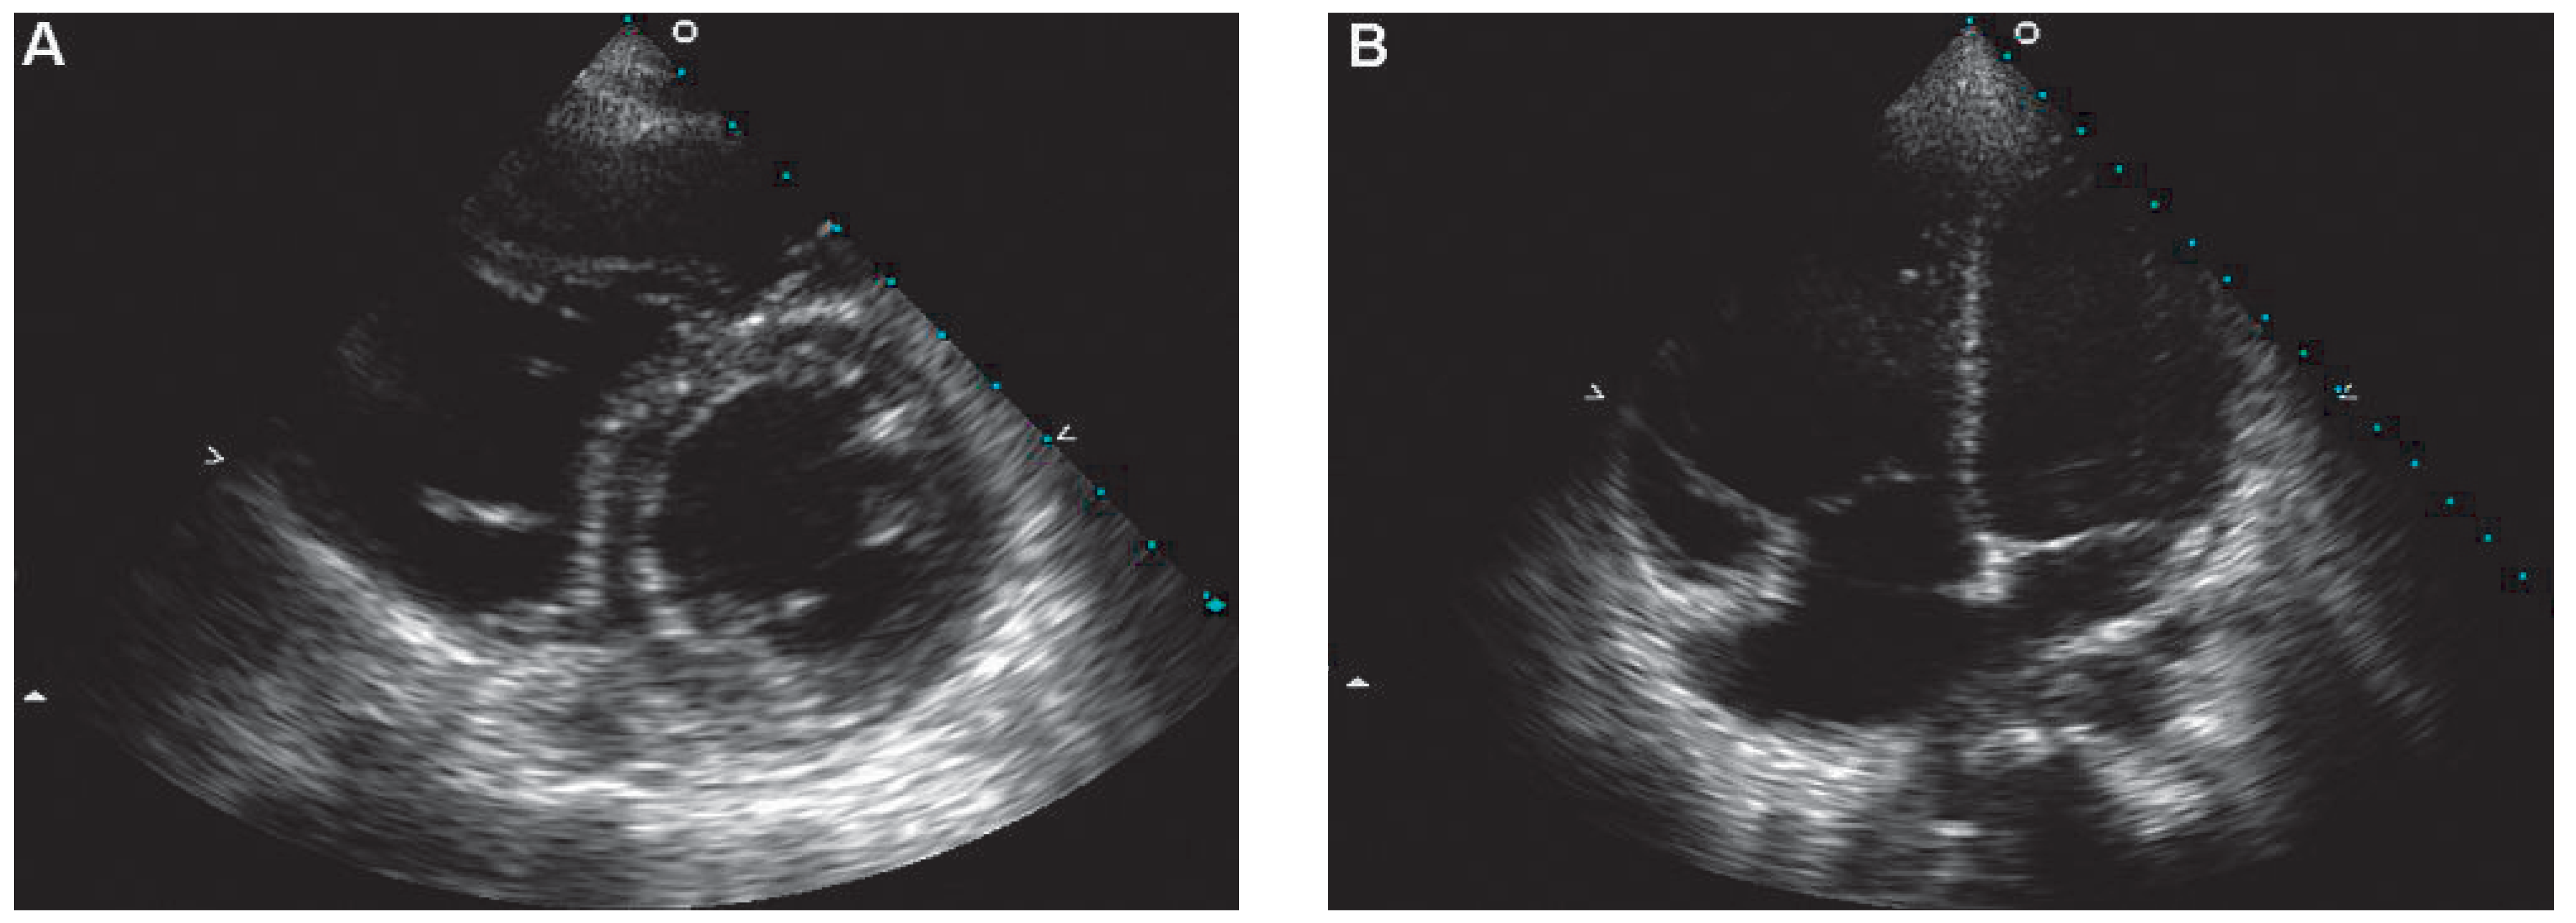

Figure 2.

Transthoracic echocardiogram performed on admission. Parasternal short axis (A) and apical four-chamber (B) views showing a severely dilated right ventricle.

A 47-year-old female presented sudden loss of consciousness. On the arrival of the medical team the initial cardiac rhythm was ventricular fibrillation, which was successfully treated with cardiopulmonary resuscitation (CPR) and electric defibrillation. Her ECG on admission is shown below (Figure 1). A transthoracic echocardiogram showed a severely dilated and akinetic right ventricle (RV) as well as a severely hypokinetic left ventricle (Figure 2). Pulmonary embolism complicated with sudden cardiac death was suspected, and the patient was treated by intravenous thrombolysis.